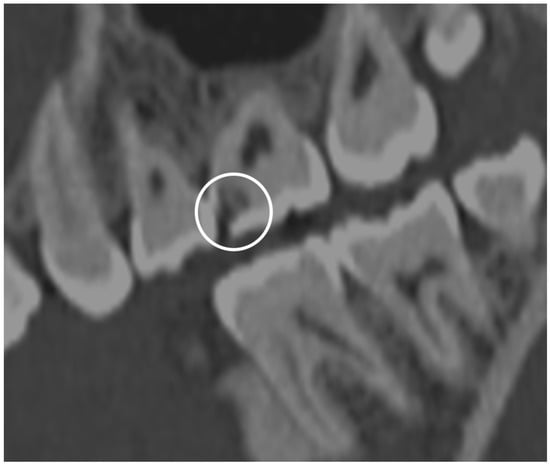

3.5.4. Periodontal Disease Radiologic Correlations